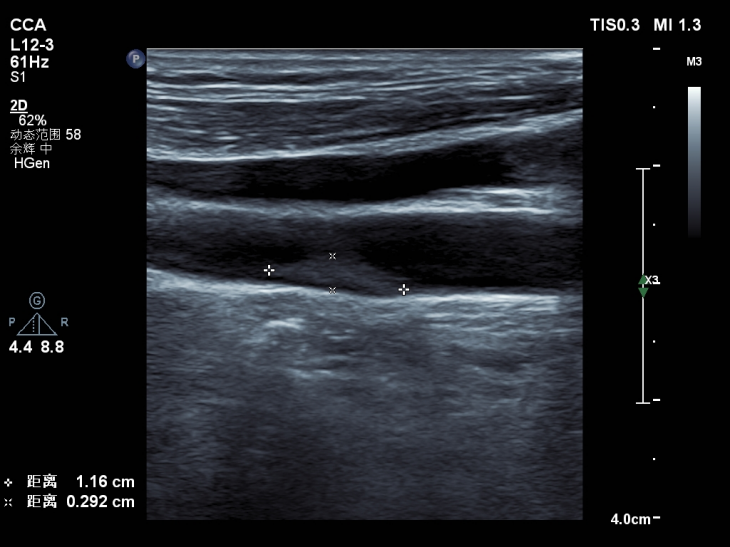

安全、快捷、準確的篩查方法——頸動脈彩超

對于頸動脈斑塊的篩查,首選頸動脈超聲!這是一種利用超聲波技術來評估頸動脈結構和功能的檢查方法。通過高頻聲波在頸動脈內的反射和散射,醫(yī)生可以清晰地觀察到頸動脈的內膜、中層和外膜結構,以及血流速度和方向等信息。

頸動脈超聲性價比高,具有無創(chuàng)、無輻射、無痛苦、重復性好等特點,不僅可以檢測頸動脈病變,還可以評估頸動脈的彈性、順應性等功能指標,為心腦血管疾病的預防和治療提供重要依據。